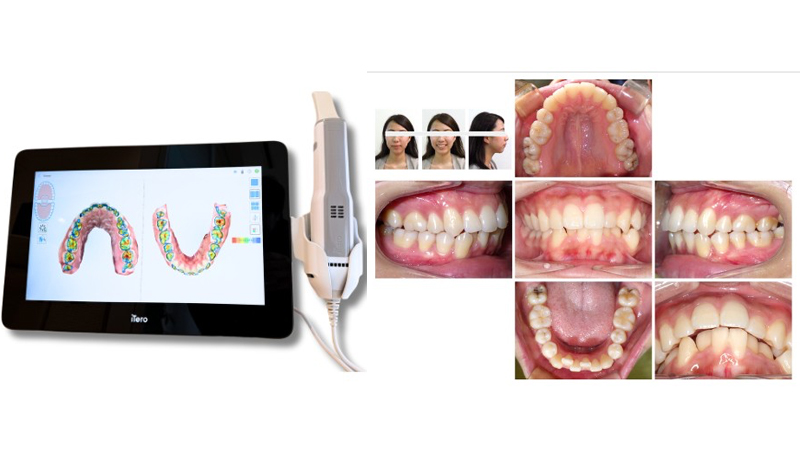

・口腔内スキャナー(iTero)による3Dスキャン

・顔貌・口腔内写真撮影

これにより、歯や骨格の状態を立体的に把握できます。